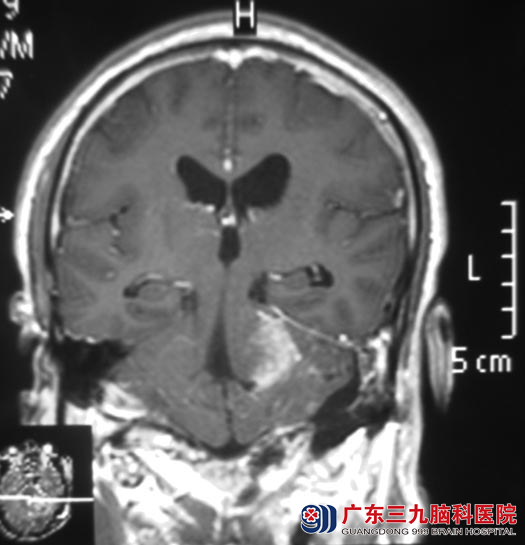

9月4日,广东三九脑科医院综合神经外科 鲁明主任主刀行“左侧听神经瘤切除术”,因肿瘤位置深入至内听道,经过8个小时的努力,成功将肿瘤全切,完整保留面神经和脑干功能。术后温先生的左耳听力较术前有明显好转,个人反应速度及走路的协调性也明显改善,未出现面瘫等其它症状。